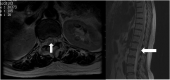

A 59-year-old female was brought to our emergency department with hypovolemic shock caused by massive bleeding from neck stab wounds inflicted by herself in a committed suicide. The patient complained of comparatively strong pain on her lower back and there was sensory and motor disturbance of bilateral lower limbs, but there was no trauma on the lumber region, the spine, or the vertebrae. After hemostasis, we performed magnetic resonance imaging, which demonstrated high intensity signal in the spinal and longitudinal area from the Th8 to the conus medullaris, and at center of the frontal horn on the upper thoracic spinal cord (owl's eye appearance) on T2 weighted images. This case was diagnosed as spinal infarction caused by low blood pressure as a result of massive bleeding. The basis of diagnosis were as follows: 1) an acute onset; 2) when the ambulance arrived, she was in hypovolemic shock caused by massive hemorrhage; 3) there was no trauma on the lumber region, the spine, or the vertebrae; 4) with CT taken on admission, aortic disease was not detected; and 5) she was not on any antipsychotic drugs which could cause thrombosis. We treated the patient following management protocol of cerebral infarction, but recovery of sensory and motor disorders was minimal.